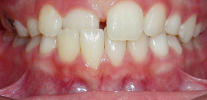

Quando gli incisivi laterali esplodono, esercitano una pressione sui denti superiori centrali che sono già comparsi, a causa della quale gli incisivi centrali divergono, formando un diastema fisiologico (cresta) e sporgendosi verso le labbra. Tuttavia, normalmente dopo l'eruzione di zanne permanenti sulla mascella superiore, il diastema si chiude. Gli ortodontisti spesso definiscono questa fase di sviluppo del sistema dentofacciale la fase "brutto anatroccolo", ma dopo la dentizione dei denti di un bambino, sia la mascella inferiore che quella superiore sono allineate.